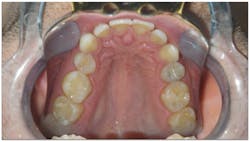

- His narrow maxilla had a corresponding vaulted palate, which is clearly visible (figure 3).